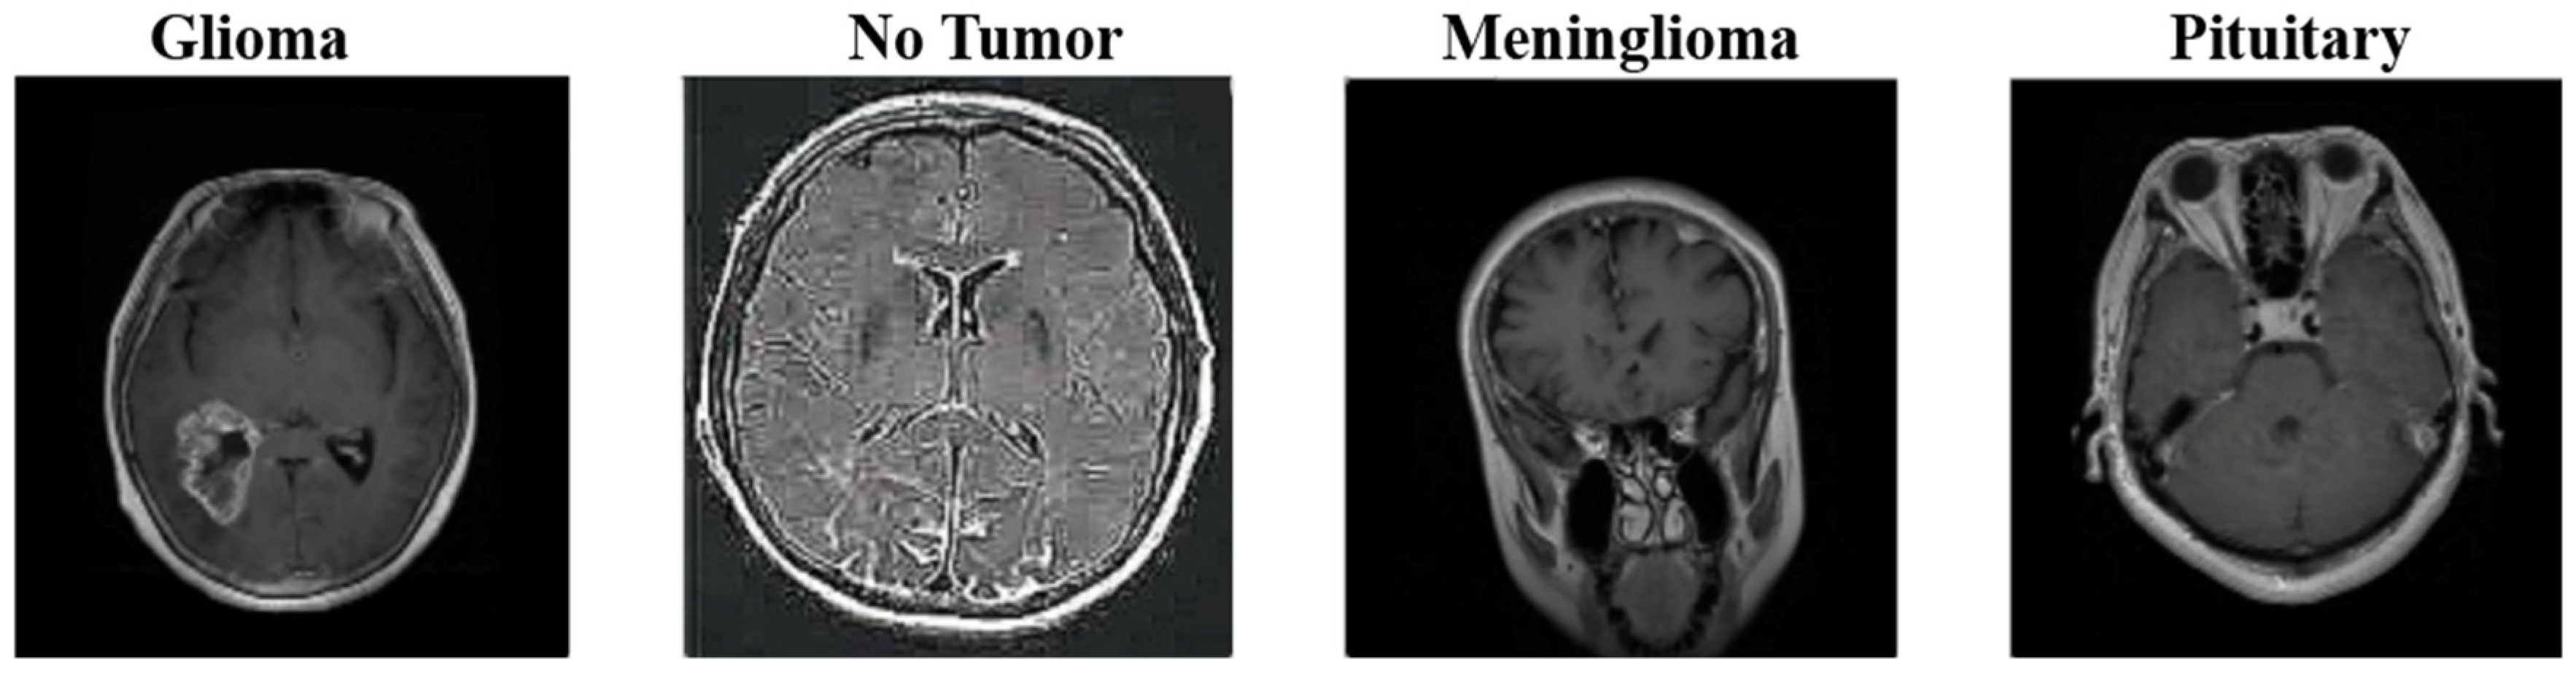

An open-source brain tumor dataset was used to analyze and evaluate our model, which was developed using different CNN architectures, as shown in Figure 3. This dataset was obtained by combining three datasets (figshare, SARTAJ dataset, Br35H) [24]. There are four classes in total in the data set. These are: brain MRI images from glioma, meningioma, oituitary, and healthy individuals. There are 1623 images for glioma, 1627 images for meningioma, 1769 images for pituitary, and 2002 images for healthy individuals. A total of 7021 MRI images were used. The dataset is open-sourced in the Kaggle application. Each file is a 512 × 512 JPEG file with a label indicating the type of brain tumor. This data set was used as input data for each model.

Figure 3.

Classes of the Dataset.